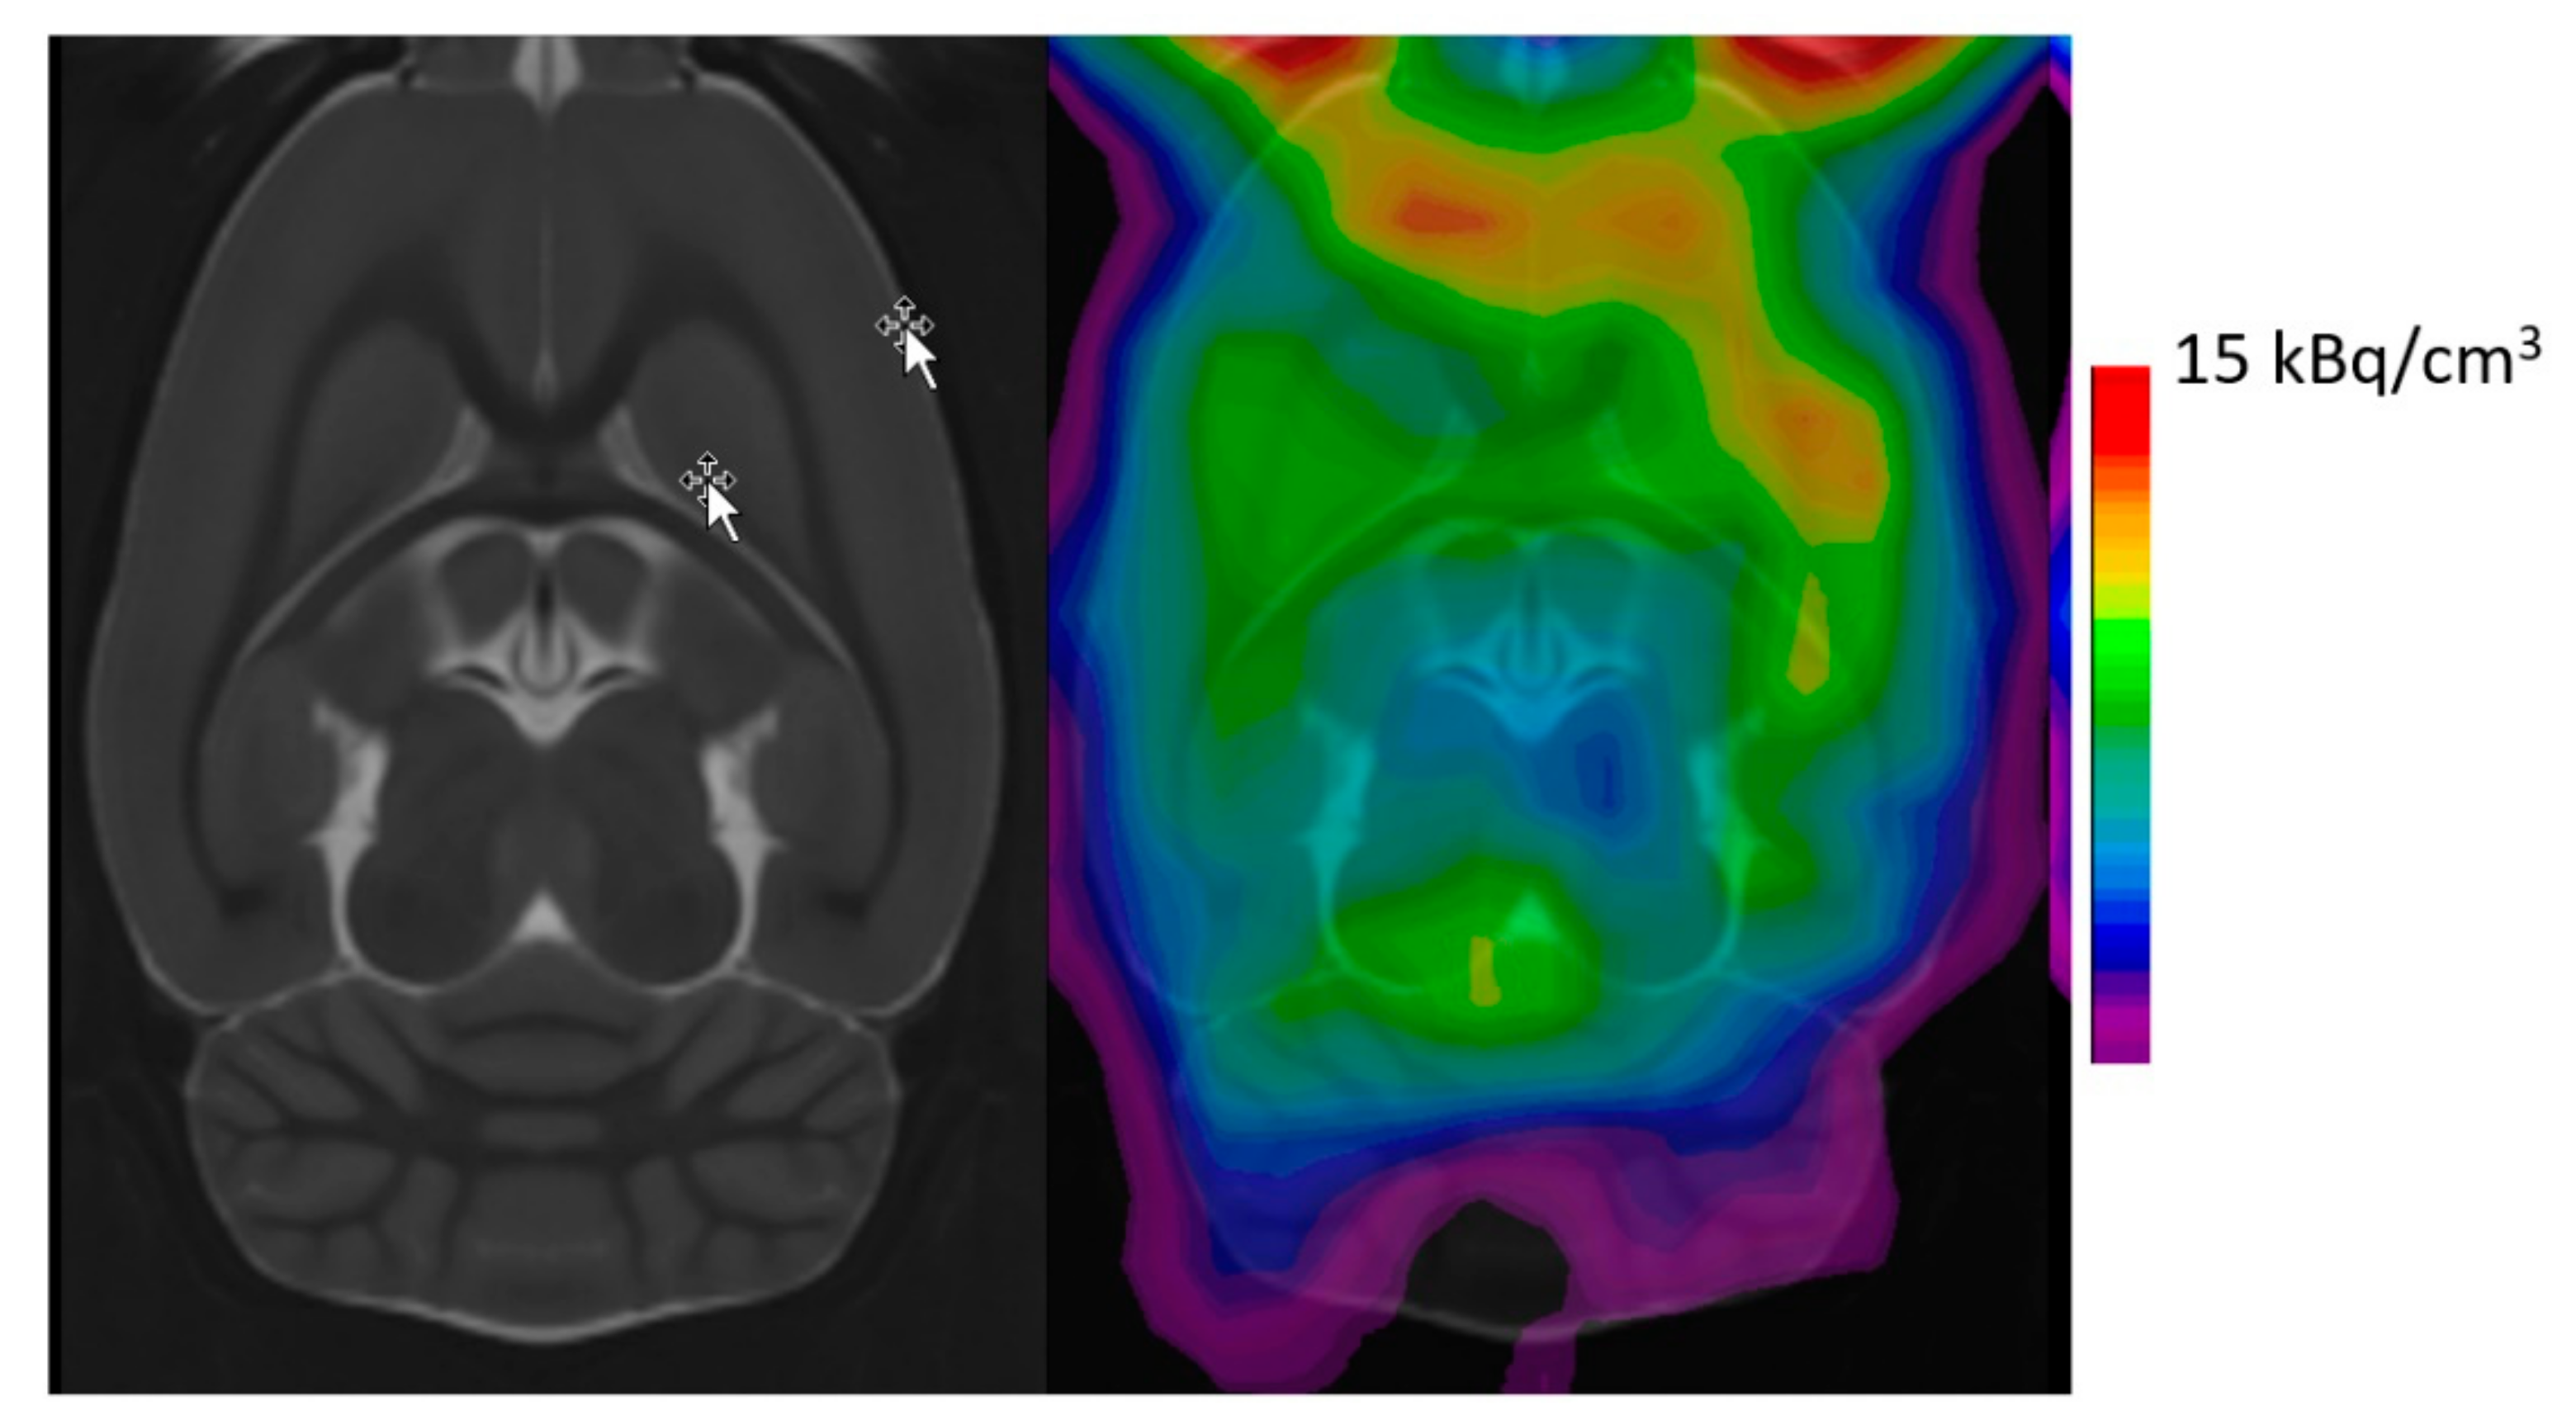

- Jorgensen, L.M.; Weikop, P.; Villadsen, J.; Visnapuu, T.; Ettrup, A.; Hansen, H.D.; Baandrup, A.O.; Andersen, F.L.; Bjarkam, C.R.; Thomsen, C.; et al. Cerebral 5-HT release correlates with [(11)C]Cimbi36 PET measures of 5-HT2A receptor occupancy in the pig brain. J. Cereb. Blood Flow Metab. 2017, 37, 425–434. [Google Scholar] [CrossRef]

- Raval, N.R.; Johansen, A.; Donovan, L.L.; Ros, N.F.; Ozenne, B.; Hansen, H.D.; Knudsen, G.M. A Single Dose of Psilocybin Increases Synaptic Density and Decreases 5-HT2A Receptor Density in the Pig Brain. Int. J. Mol. Sci. 2021, 22. [Google Scholar] [CrossRef]